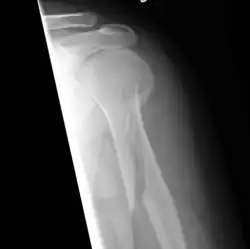

Fractura espiroidea

En medicina y traumatología, se designa con el nombre de fractura espiroidea a aquella fractura ósea en la cual la línea de fractura sigue una dirección espiral en relación con el eje principal o longitudinal del hueso. Se llama en ocasiones fractura por torsión en base al mecanismo de producción. Afecta fundamentalmente a los huesos largos como el húmero y la tibia.[1]

Las fracturas espiroideas se producen como consecuencia de la aplicación de una torsión sobre el hueso, de tal forma que una fuerza tiene un sentido y otra el sentido contrario, el hueso tiende a retorcerse sobre sí mismo hasta que la fuerza aplicada supera su resistencia elástica, produciéndose una línea de fractura que tiene un trayecto espiral. La torsión se define como la deformación que sufre un objeto, en nuestro caso un hueso, como consecuencia de una fuerza que le imprime un movimiento de rotación sobre su eje, estando un extremo fijo. Este mecanismo explica claramente la fractura de tibia por torsión en las que la pierna gira sobre sí misma, permaneciendo el pie inmóvil sobre el suelo.